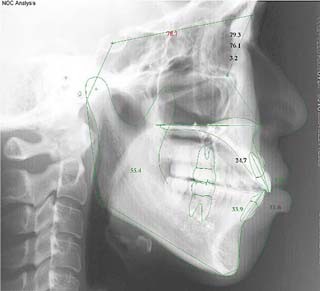

(開咬/叢生/非抜歯/リンガルブラケット矯正装置)

装置撤去です。動的処置は2年弱でした。十分とは言えない点もありますが、患者希望による非抜歯配列でしたので、概ね良好と言える結果が得られたと思います。まだ、オーソアンカー SMAPがそのまま残っているのが見えますが、もう必要ないので撤去して貰う予定です。今後は保定治療に移行し、咬合の安定状態を管理していきます。